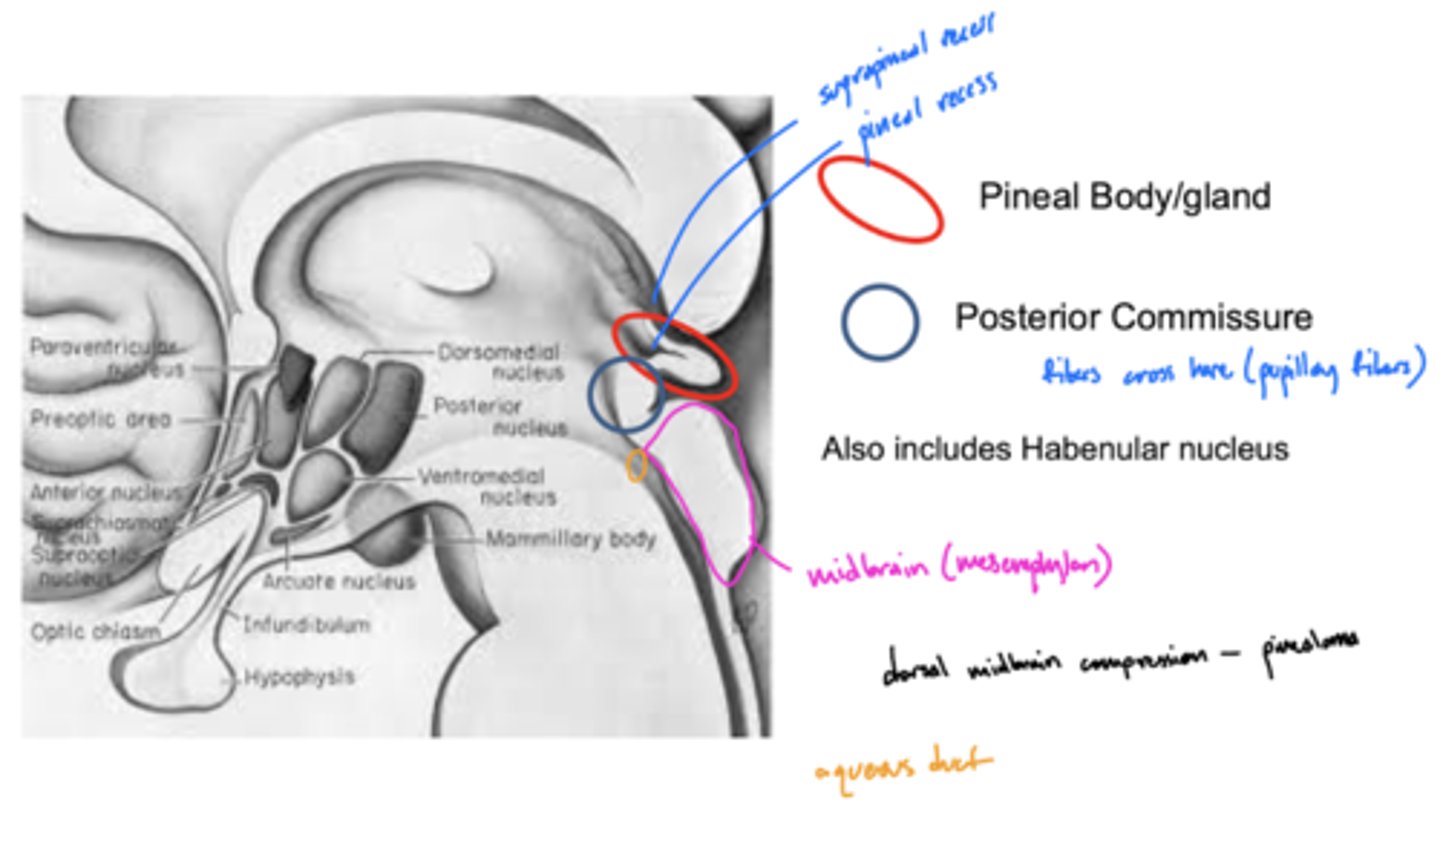

What is the primary nuclei of the epithalamus?

pineal body/gland

What structure is directly inferior to the pineal body of the epithalamus?

posterior commissure

What is the function of the posterior commissure?

largely unknown -- but... pupillary fibers cross here maybe light pupillary response

What is the function of the pineal gland of the epithalamus?

produces melatonin (and responsible for circadian rhythms)